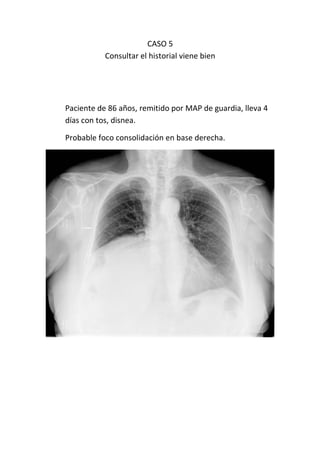

Este documento presenta 7 casos de patología torácica que serán discutidos en una sesión de interpretación radiológica. El objetivo es que los asistentes tomen notas aclaratorias durante la discusión interactiva de cada caso, en lugar de una mera explicación teórica. Los casos incluyen agenesia pulmonar derecha, situs inversus, estridor, neumonía con hemoptisis y enfermedad intersticial. El último caso involucra a un paciente de 86 años con tos y disnea que podría tener una consolidación en la base